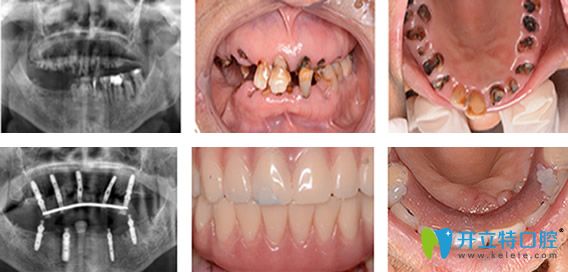

1950后 / 程阿姨

職業(yè):單位退休職工 癥狀:全口牙缺失

需求:種一口好牙檢查與診斷:牙槽骨缺損嚴(yán)重

種植方案:牙槽骨骨量修復(fù),德國ICX全口種植

主診醫(yī)生:劉旭光

種植牙過程及結(jié)果展示: